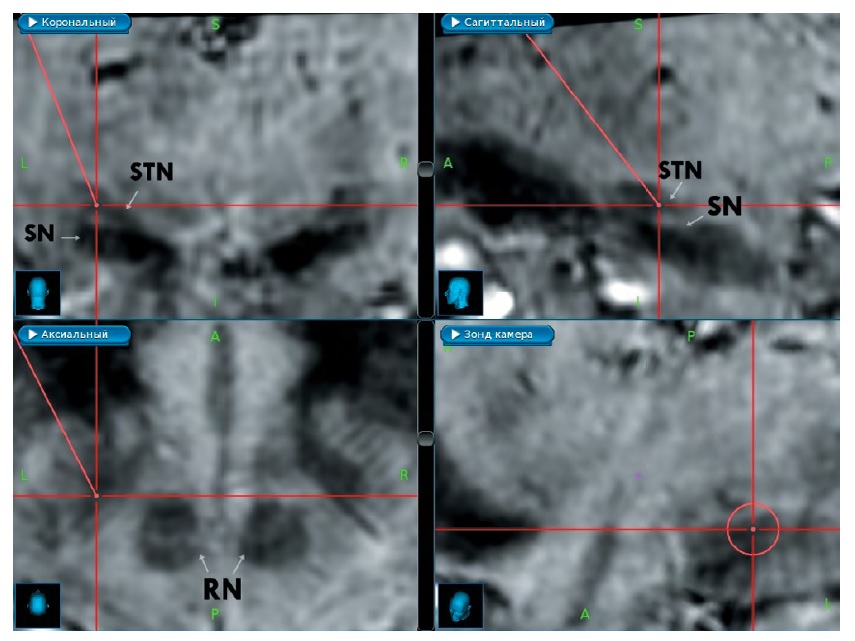

Всем пациентам была проведена предоперационная 3 Т МРТ в режимах T1 FSPGR BRAVO, T2 HIGH-RES, FLAIR и SWAN. Изображения совмещались на станции планирования «StealthStation S7» («Medtronic»). Расчётную точку цели (РТЦ) определяли по совокупности атлас-ориентированного, непрямого и прямого методов. На первом этапе расчёты проводили на основании стандартных координат (12 мм латерально, 2 мм кпереди и 4 мм книзу от середины межкомиссуральной линии). На втором этапе корректировали переднезаднюю координату относительно передней границы красного ядра. На третьем этапе координаты были скорректированы по результатам прямой визуализации СТЯ. Определялись верхняя и нижняя границы ядра, что позволило принять за РТЦ середину СТЯ (рисунок).

Прямая визуализация СТЯ в режиме SWAN 3 T. Белыми стрелками обозначены: STN — субталамическое ядро, SN — черная субстанция, RN — красное ядро. Косая красная линия обозначает расчётную траекторию электрода и заканчивается в РТЦ. Горизонтальная красная линия проходит через передний край красных ядер на уровне середины STN. / Direct visualization of the STN in 3T SWAN mode. White arrows represent: STN — subthalamic nucleus, SN — substantia nigra, RN — red nucleus. The diagonal red line represents the calcula- ted trajectory of the electrode and finishes in the estimated target point. The horizontal red line passes through the anterior edge of the red nuclei at the level of the middle of the STN.